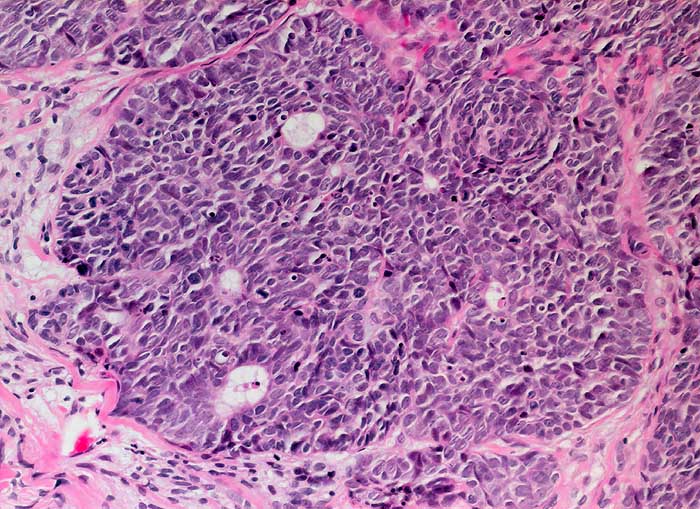

Die Tumorzellen liegen einzeln oder in kleinen Verbänden und ganzen Gewebsfragmenten. Die polymorphen Kerne sind vergrössert und enthalten verklumptes unregelmässig verteiltes Chromatin und grosse Nukleolen. Gut differenzierte Karzinome erkennt man am breiten und oft verhornten Zytoplasma. Längliche bis fadenförmige Tumorzellen mit pyknotischen Kernen können als einziger Hinweis auf das Vorliegen eines Karzinoms vorhanden sein. Wenig differenzierte Karzinome haben polymorphe und schlechter erhaltene Kerne. Der Hintergrund ist meist detritisch und oft hämorrhagisch. Ulzeration, Einblutungen und bakterielle Infektionen beeinflussen den Erhaltungszustand und die Art der abgestrichenen Zellen. Ist die Oberfläche eines ulzerierten Karzinoms von einem Fibrinschorf bedeckt, enthalten die Ausstriche lediglich Detritus, Granulozyten und Erythrozyten, aber keine Tumorzellen. Die Sensitivität für die Karzinomdiagnose ist aus diesem Grund geringer als für die Diagnose eines Carcinoma in situ.

Unten werden drei Fallbeispiele mit histologischer Korrelation gezeigt.